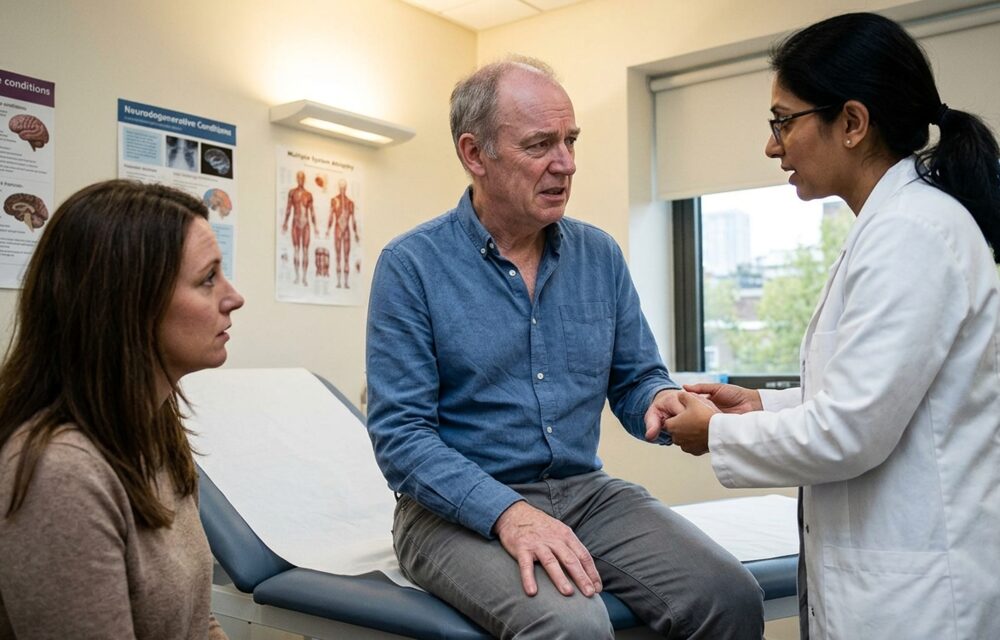

٭حمل سے قبل اور اس دوران باقاعدگی سے معائنہ کرواتی رہیں۔ اس سے ممکنہ پیچیدگیوں کی تشخیص اور خاتمہ کیا جا سکتا ہے۔

٭وزن، ذیابیطس اور ہائی بلڈ پریشر کو کنٹرول کرنے کے لیے ڈاکٹر کی ہدایات پر عمل کریں۔

٭بار بار ڈاکٹر نہ بدلیں۔ ایسا کرنا ضروری ہو تو نئی ڈاکٹر کو پرانی تفصیلات اور رپورٹوں سے آگاہ کریں۔